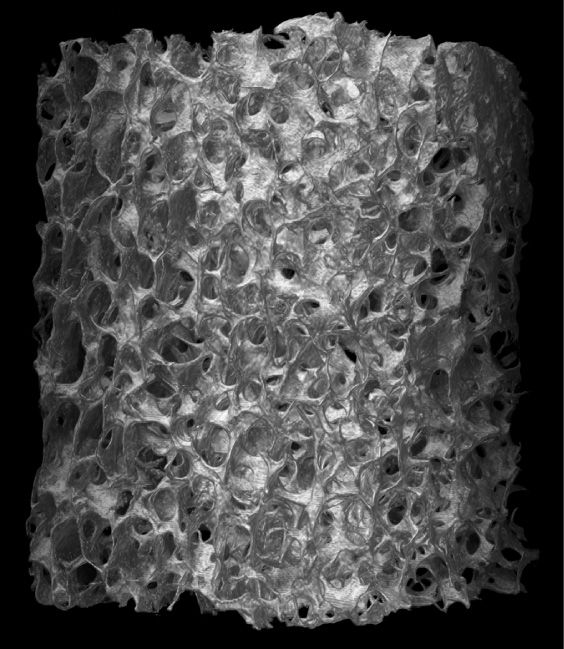

Matrix OI® is a Stem Cell Containment® human scaffold that is processed using CellRight's proprietary BioRinse™ technology. All Matrix OI® products are verified for osteoinductivity post-sterilization prior to release for distribution. In-vivo test results demonstrate all 5 bone-forming elements present (chondrocytes, osteocytes, bone marrow cells, cartilage, and new bone) in our implants. The product's revolutionary design uses Geometric Compression™ that minimizes the use of fixation devices that support graft placement. The product's pliable handling characteristics facilitate minimally invasive patient and surgeon preferred surgical procedures. Micro-CT scans of this human scaffold exhibit a well-interconnected matrix that preserves the infrastructure of the graft to maximize intra-cellular growth for bone repair.